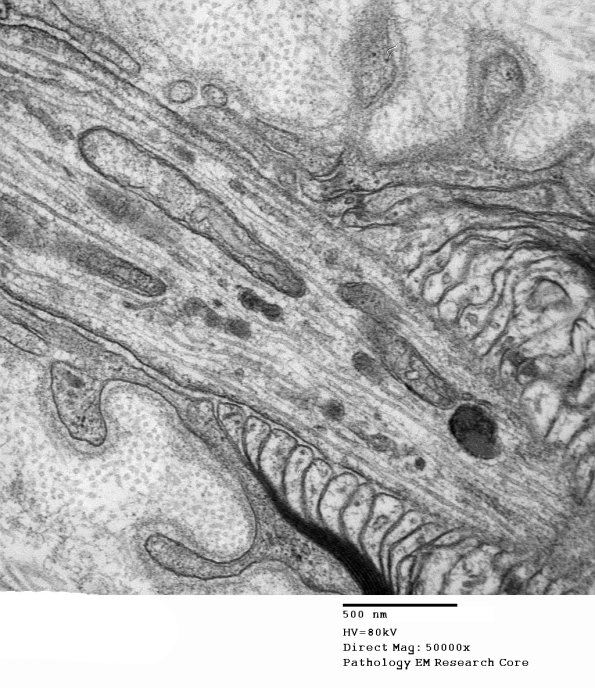

Washington University Experience | PERIPHERAL NEUROPATHY | 3 NORMAL MYELIN & SCHWANN CELLS | 2 Node of Ranvier | 11A4 Normal Node of Ranvier (Case 9) EM A_171 - Copy

Notice the node is enclosed in the Schwann cell basal lamina. (electron micrograph)